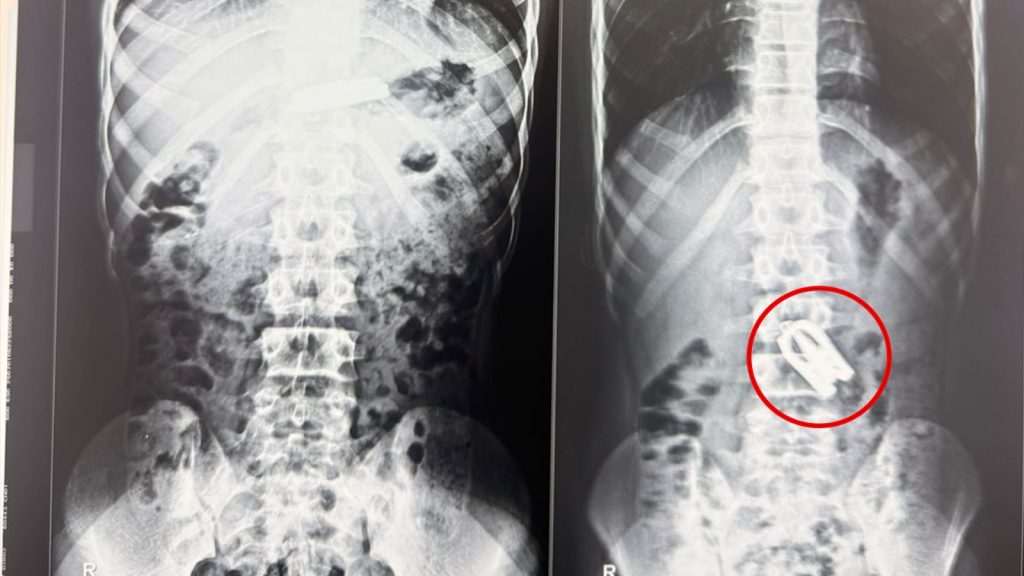

आकस्मिक कक्षमा गरिएको एक्स–रे र सिटी स्क्यानको आधारमा उनको पेटको सानाे आन्द्राकाे जेजुनुम भित्र कैंची अड्किएको पुष्टि भयो। घटना अत्यन्तै जटिल र संवेदनशील रहे पनि, नोबेल शिक्षण अस्पतालका वरिष्ठ ल्याप्रोस्कोपिक सर्जन डा. अमित भट्टराई र उनको दक्ष सर्जिकल टोलीले ल्याप्रोस्कोपिक प्रविधिको सहायताले सफलतापूर्वक शल्यक्रिया गरी कैंची निकालेका छन्। डा. भट्टराईका अनुसार, “बालकको आन्द्रामा कैंची अड्किएर त्यसले थप जटिलता ल्याउन सक्थ्यो, तर समयमै ल्याप्रोस्कोपिक सर्जरीमार्फत निकाल्न सफल भयौँ। अहिले बिरामीको अवस्था स्थिर छ।”